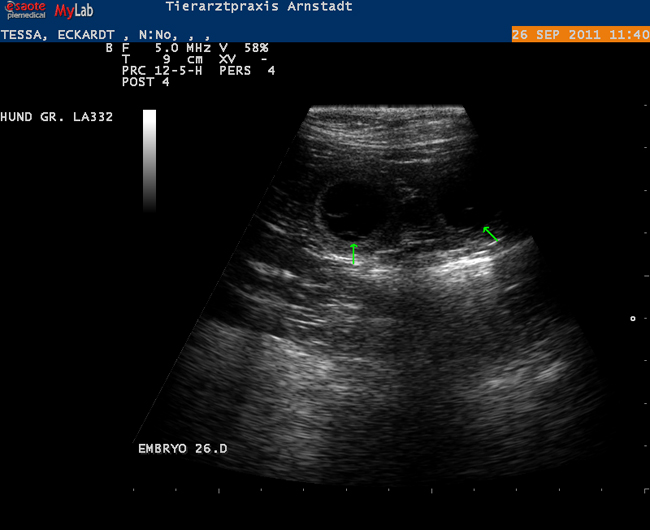

Die Untersuchungstechnik mittels Ultraschall ist insbesondere im Weichteilgewebe geeignet, Befunde zu erheben.

Wir führen in unserer Praxsis abdominale sowie kardiologische Ultraschalluntersuchungen durch.

Beispiele: